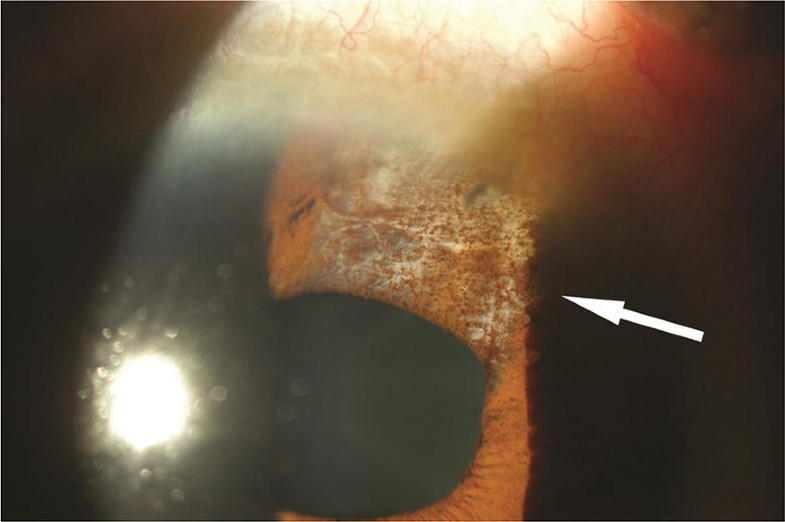

Herpes simplex uveitis Large pigmented keratic precipitate… Flickr Herpes Simplex Uveitis Ocular herpes simplex virus (hsv) infections can cause inflammation of the retina (retinitis), iris and associated uveal tract (iritis or uveitis), cornea. It's important to get treatment because it can sometimes affect your sight. A herpes simplex eye infection is a viral infection that can cause a painful, red eye. However, there are some things that can cause uveitis. Often. Herpes Simplex Uveitis.